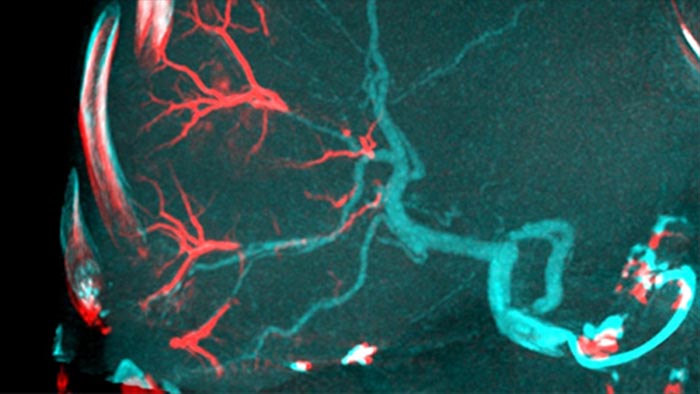

TACEやSIRTなどの化学/放射線塞栓療法の採用により、標準化と効率化の必要性が高まります。どの症例でも、腫瘍の位置を確実に一貫して特定し、必要な栄養血管を特定し、適切なインターベンションアプローチを計画/実行する必要があります。 フィリップスの栄養血管の自動検出ソリューションを使用すると、コーンビームCTのみを使用する場合に比べて栄養動脈の検出が大幅に改善されます。EmboGuideは、ユーザーの感度を高め、誤検出を減らし、術者間の能力差を最小にできる可能性があるため、TACE処置の有効性を最大限に高めるのに役立ちます。¹

適切な治療を決定するには、肝癌小結節陰影を区別し、小さな栄養血管を特定する能力が不可欠です。病変部のセグメンテーションを行い、すべての栄養血管へとナビゲートすることで成功の機会が増加します。患者がカテーテル寝台の上にいる間に治療エンドポイントと治療の結果を確認できるため、臨床転帰が向上します。